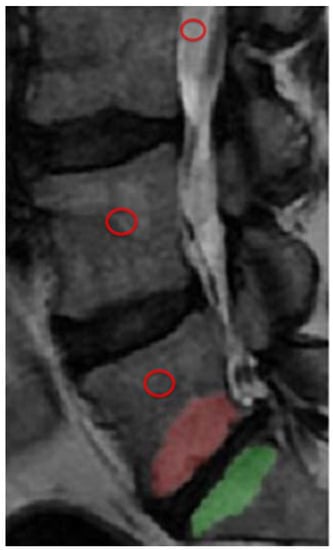

2.3. Measurements

3. Results

Figure 1. Illustration of Modic change (MC) segmentation in L5 and S1 and placement of ROIs (red circles) in cerebrospinal fluid, vertebrae without MC, and vertebra with MC.